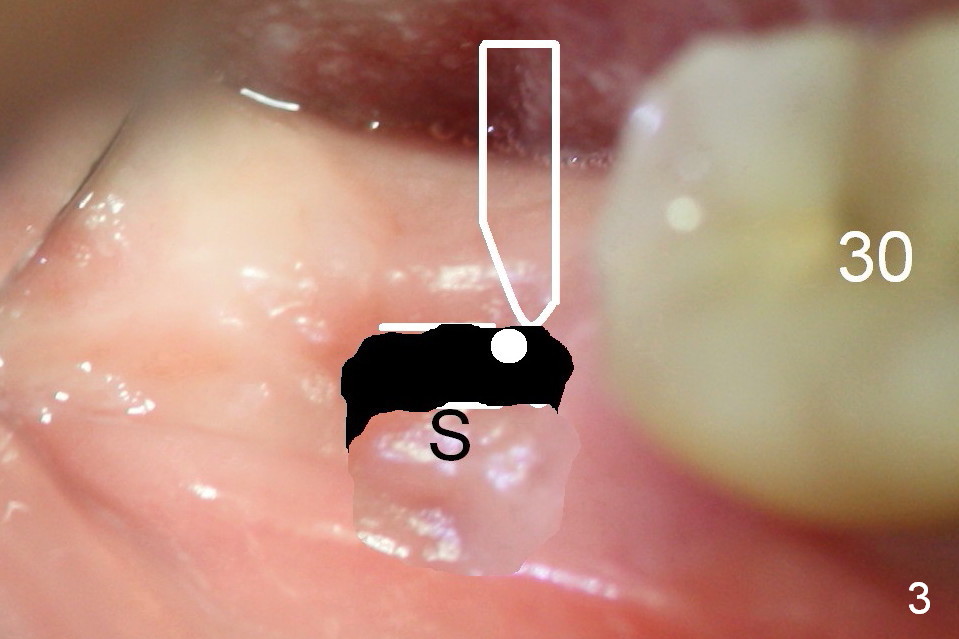

Steps of Bone Expansion (Illustration)

After incision and flap elevation, use #15 blade (Fig.1 white outline) to start bone expansion as lingual as possible (white line). Use bone scalpels, bone blades and D osteotomes to push the bone buccally (Fig.2 arrow). Use 2 mm pilot drill to initiate osteotomy as lingual and mesial as possible (Fig.3 white circle). The next step is to use bone expanders as apical as possible (Fig.4 white circle). If the apical bone is hard, use drills at 50 RPM (to collect bone).